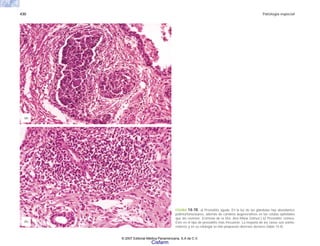

ÓRGANO NEOPLASIA SECRECIÓN EFECTO

Hipófisis Adenoma o carcinoma Una o varias hormonas Acromegalia